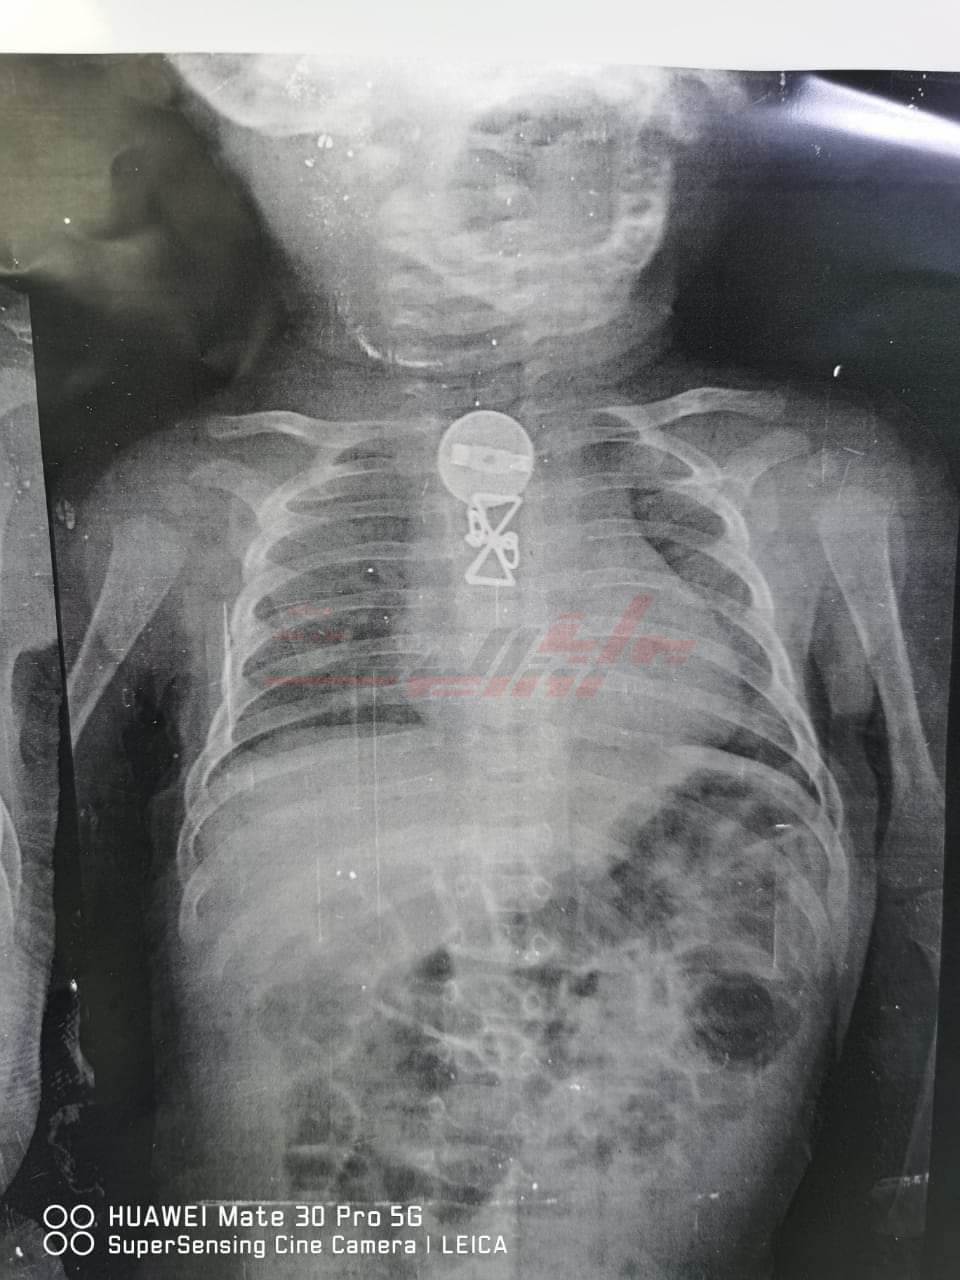

نجح فريق طبي بمستشفى الأطفال التخصصى ببنها، برئاسة الدكتور محمد محمد متولي استشاري جراحة الأطفال ونائب المدير العام وبمعاونة نخبة من أطباء الجراحة، والتخدير بالمستشفى وهم كل من الدكتور مصطفى حمد، والدكتور  محمد سعدة، والدكتور وليد محمد، والدكتور إسلام حجاب باستخراج جسم غريب من طفل يبلغ من العمر ثلاثة أشهر.

وأشار رئيس الفريق الطبي، إلى أن المستشفى استقبل الطفل وكان يعاني من التنفس وتم حجزه بالمستشفى وعمل الأشعات اللازمة، وتبين وجود جسم معدني داخل الجسد، وتم استخراجه، وتم العرض على والديه اللذين أقرا أن شقيقته الكبرى كانت تداعبه، وقام ببلع ذلك الجسم المعدني منذ فترة.